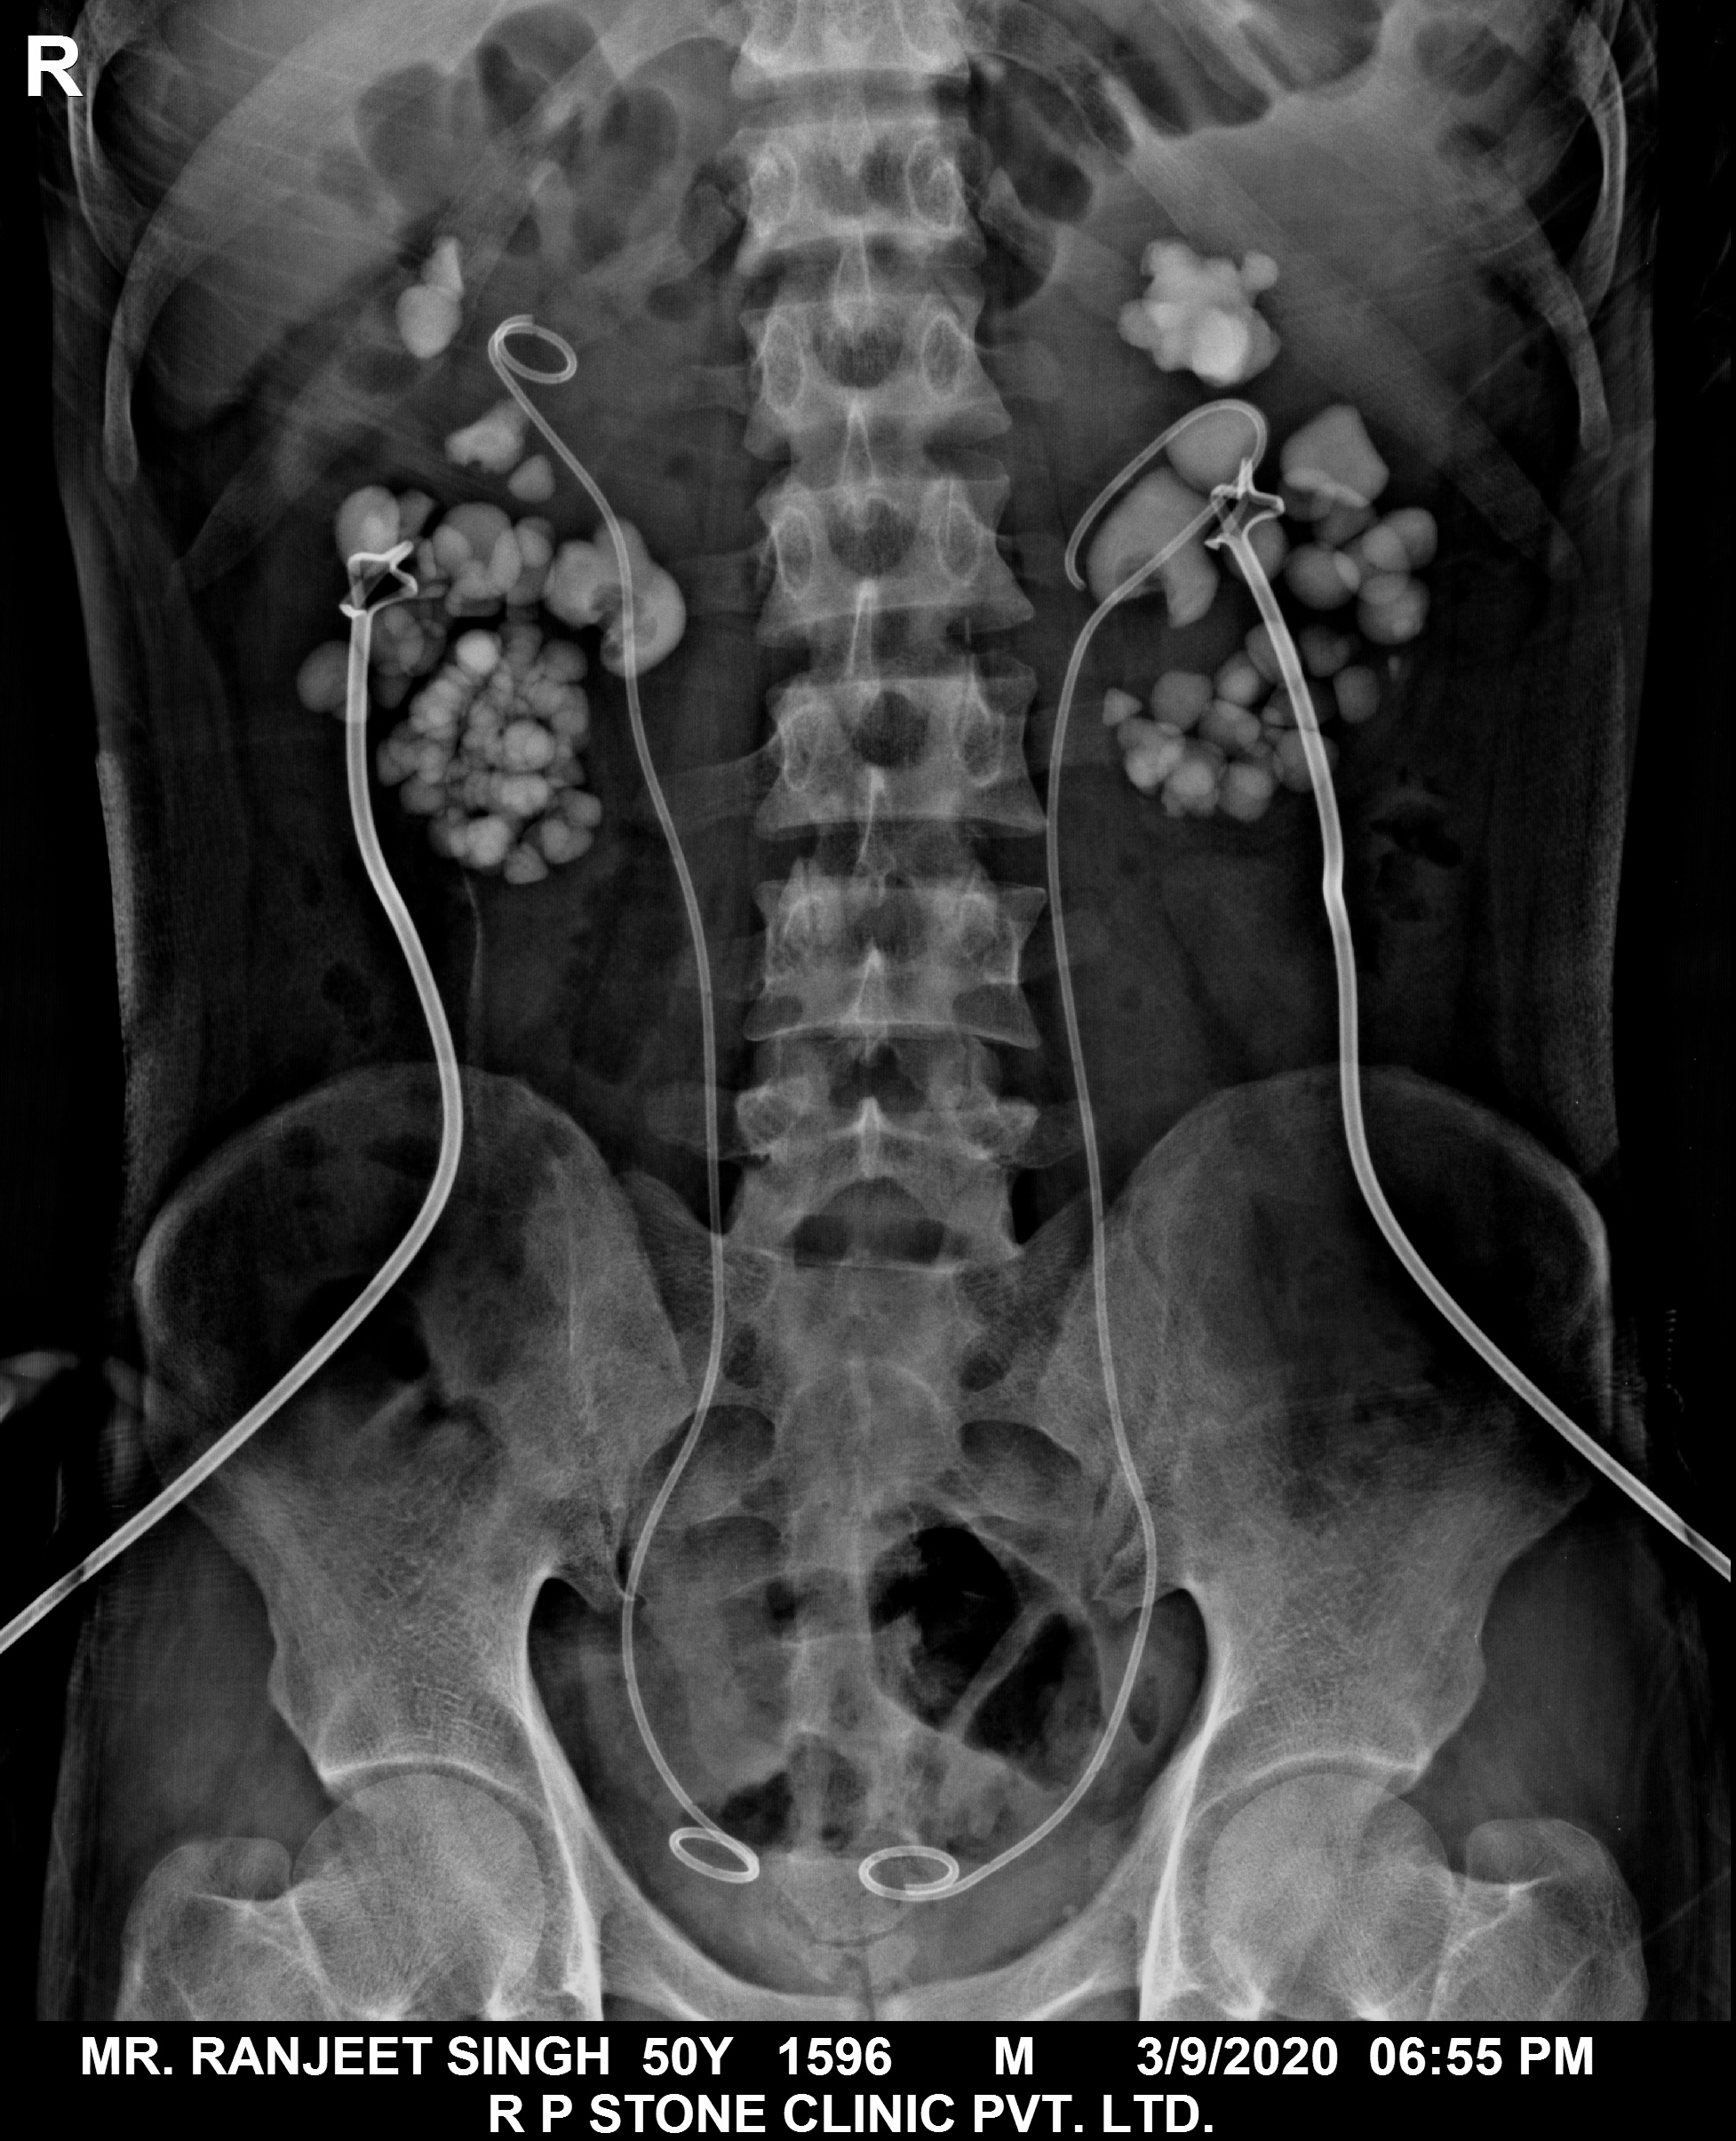

The Images Below are of Kidney Stones taken as snapshots from the video recording of RIRS Surgery done at our hospital with Digital Flexible Ureteroscopes, Flex XC and Flex XC S.